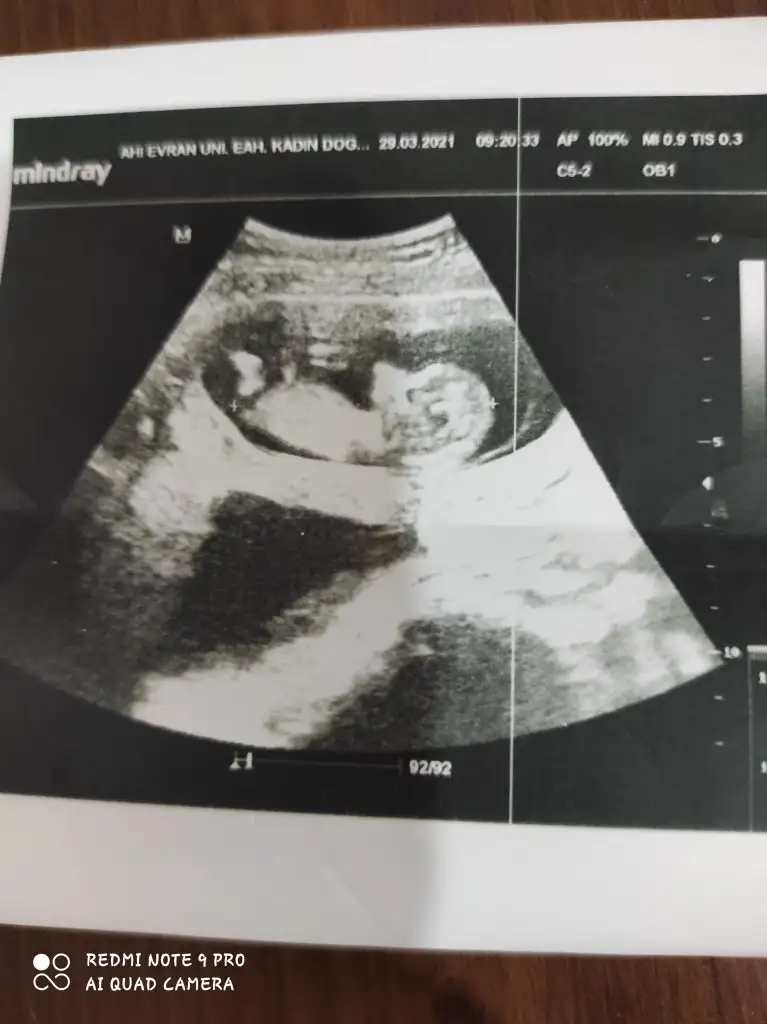

12 haftalıkKac haftalık 11 12 13 haftalar olmalı kız sanki

Dr + getirmiş nubuna görülmüyor tipi kız gibi sanki 11-12 hafta varsa paylaşın